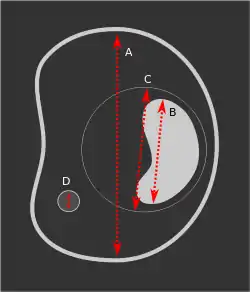

The gestational sac is the large cavity of fluid surrounding the embryo. During early embryogenesis it consists of the extraembryonic coelom, also called the chorionic cavity. The gestational sac is normally contained within the uterus. It is the only available structure that can be used to determine if an intrauterine pregnancy exists until the embryo can be identified.

On obstetric ultrasound, the gestational sac is a dark (anechoic) space surrounded by a white (hyperechoic) rim.

The gestational sac is spherical in shape, and is usually located in the upper part (fundus) of the uterus. By approximately nine weeks of gestational age, due to folding of the trilaminar germ disc, the amniotic sac expands and occupy the majority of the volume of the gestational, eventually reducing the extraembryonic coelom (the gestational sac or the chorionic cavity) to a thin layer between the parietal somatopleuric and visceral splanchnopleuric layer of extraembryonic mesoderm.

The yolk sac and embryo should be readily identifiable when the gestational sac reaches a certain size — a yolk sac should be seen when the gestational sac is 20mm and a fetal pole should be seen when the gestational sac reaches 25mm.